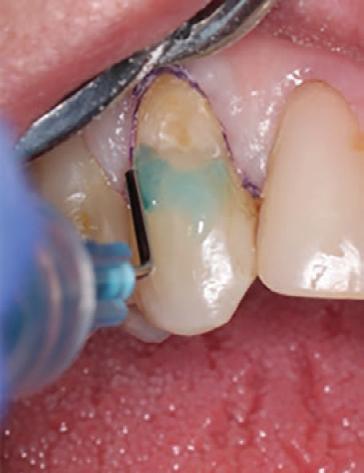

Etching and Bonding

Selective etching of the enamel was performed using a phosphoric acid etchant, followed by rinsing and air drying (Fig. 5). CLEARFIL™ Universal Bond Quick 2 was then applied according to the manufacturer’s protocol: a three second application, gentle airdrying, and light-curing for 20 seconds (Fig. 6).

Figure 5. Selective etching of the enamel at the margins.

Figure 6. Application of CLEARFIL Universal Bond Quick 2 following selective etching of the enamel margins.